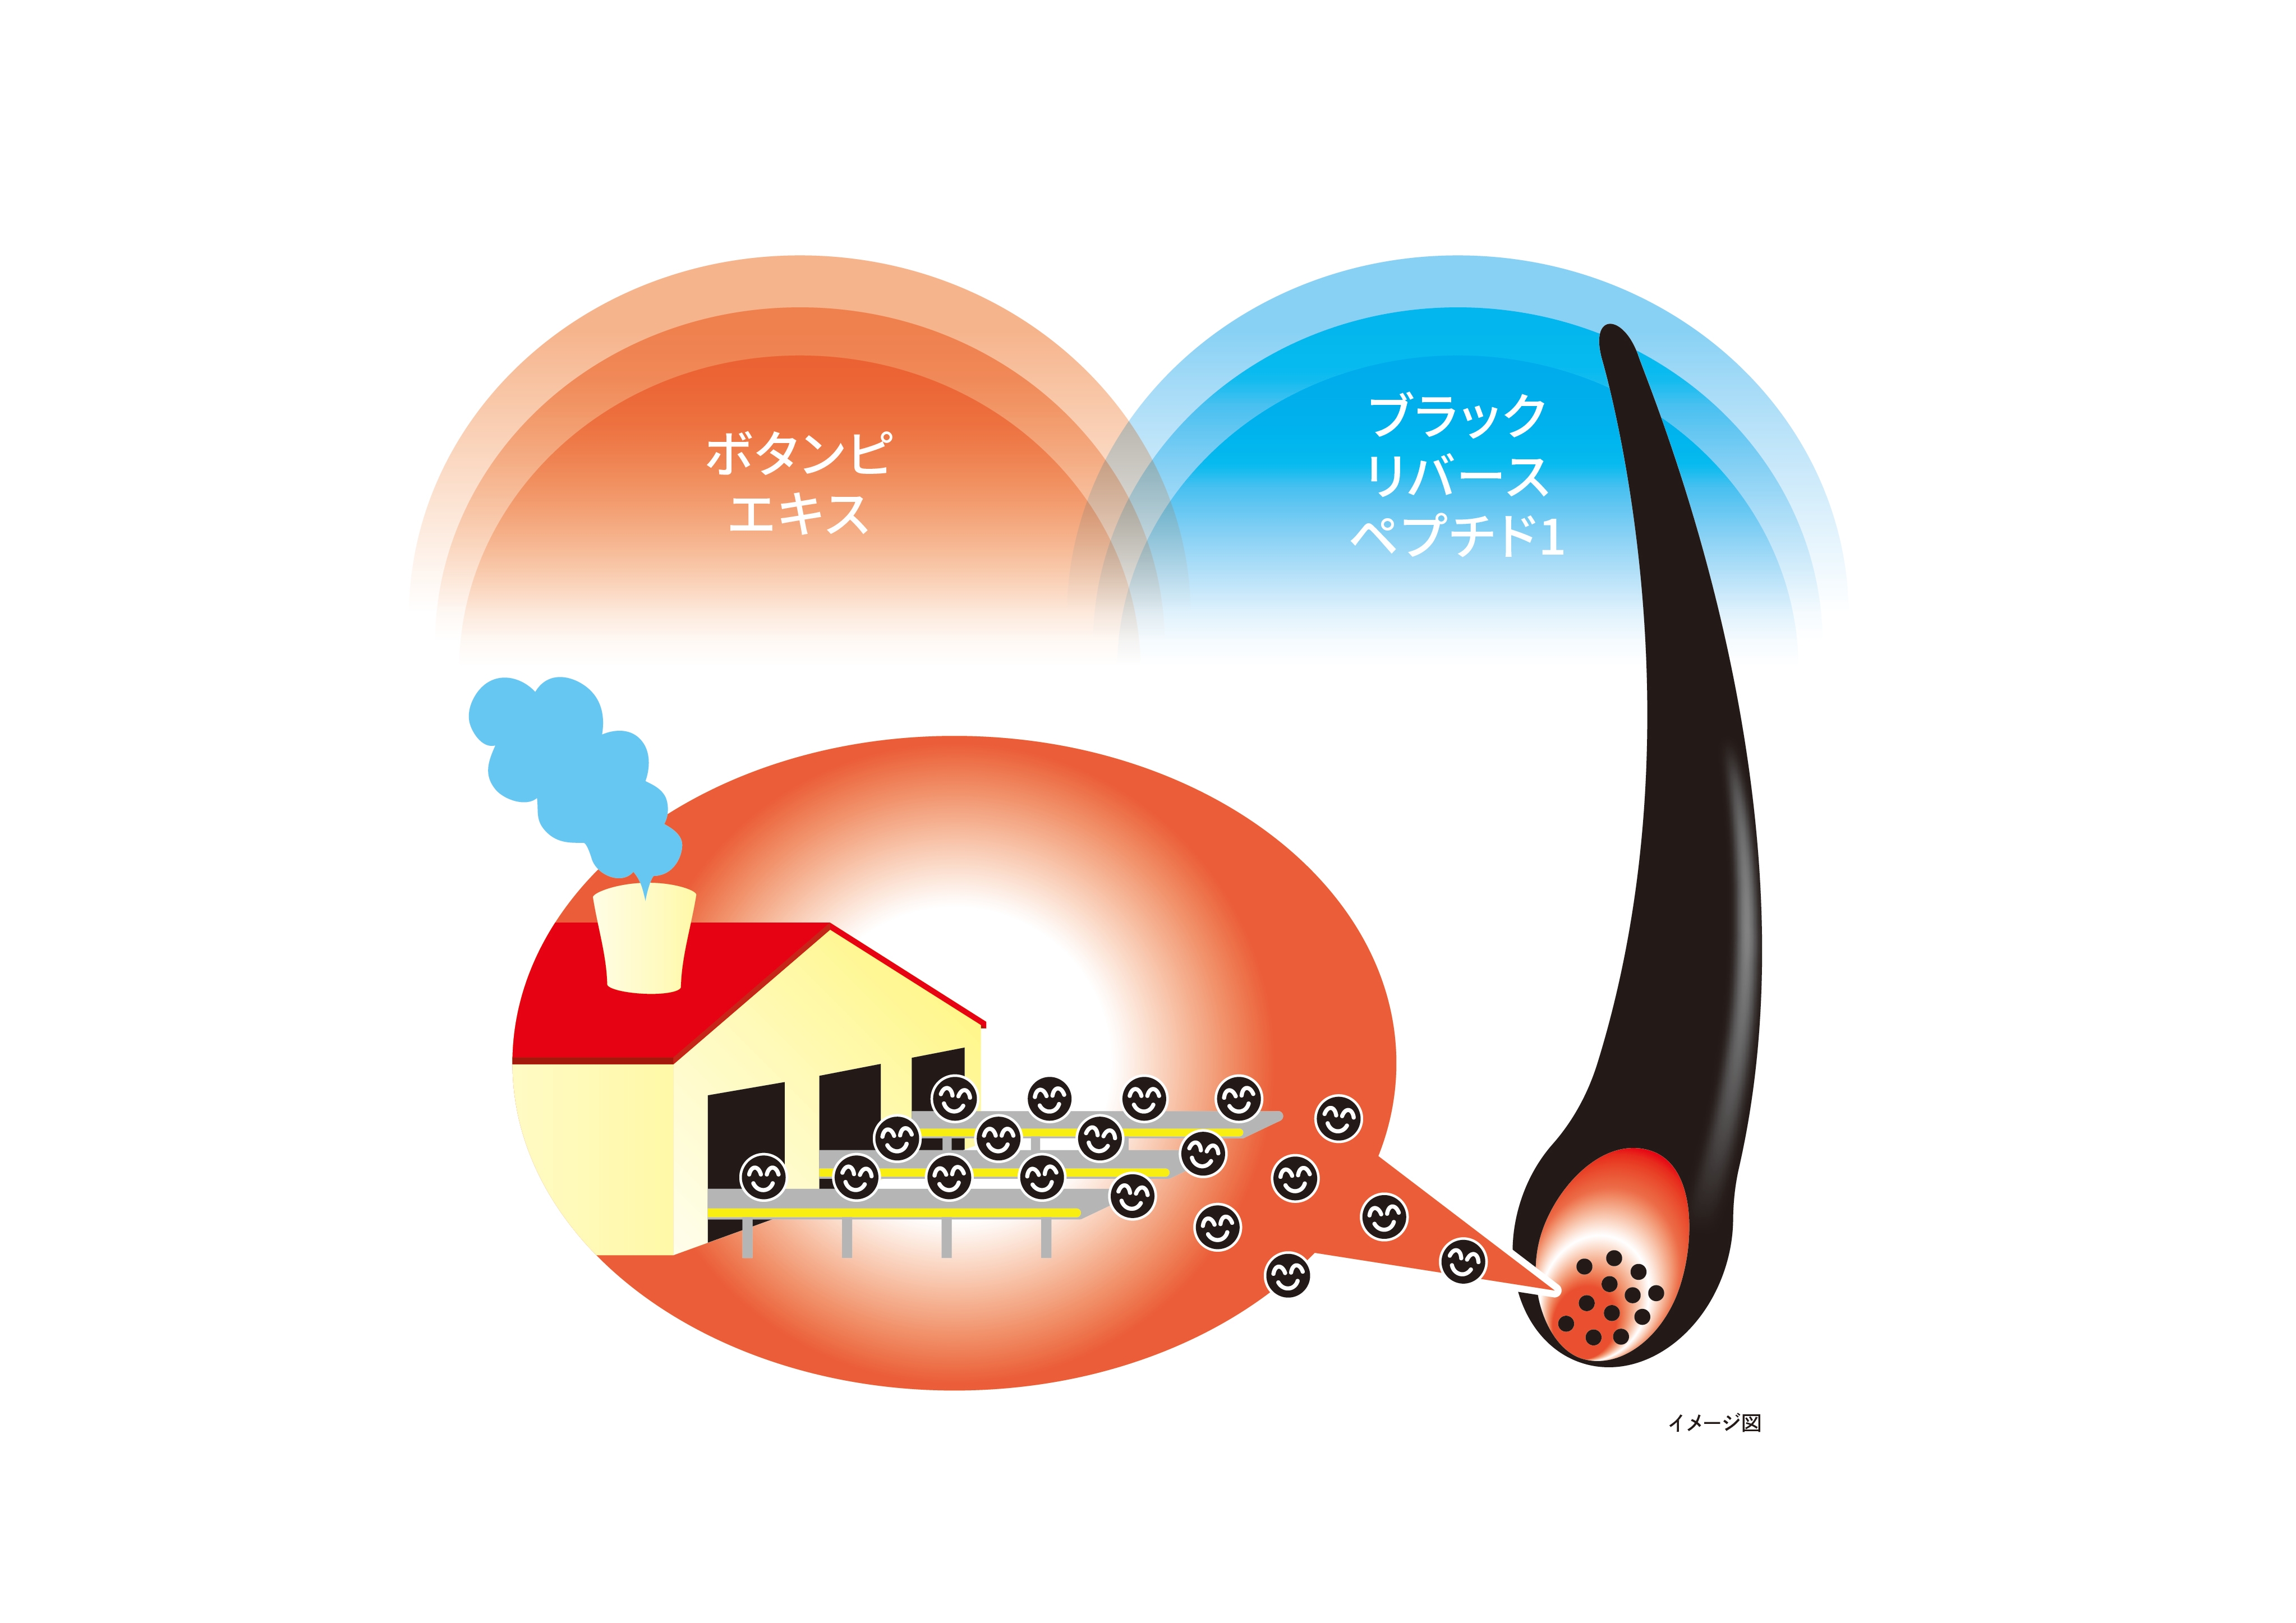

大正製薬株式会社(以下、当社)は、これまでボタンピエキス※1とブラックリバースペプチド1の組み合わせが、メラニンを作ることによって白髪改善効果を示すということを確認してきました。

当社はこのたび、Monasterium Laboratory(ドイツ・ミュンスター)※2、株式会社ネイチャーラボと共同で、新たにボタンピエキスとブラックリバースペプチド1の白髪改善効果を示すメカニズムを確認しました。

ボタンピエキスは毛包のメラノサイトにおいて、メラニンをつくるメラノソームの構成タンパク質『Gp100』の量を増加させる傾向があることがわかりました。

さらにボタンピエキス及びブラックリバースペプチド1を組み合わせることで、毛包内のメラニンの量を増加させることがわかりました。

ボタンピエキス及びブラックリバースペプチド1の組み合わせは、メラノサイトでメラニンを作り出すメラノソームを形成・成熟化させ、メラニンの産生を促し白髪改善作用を発揮することが期待されています。